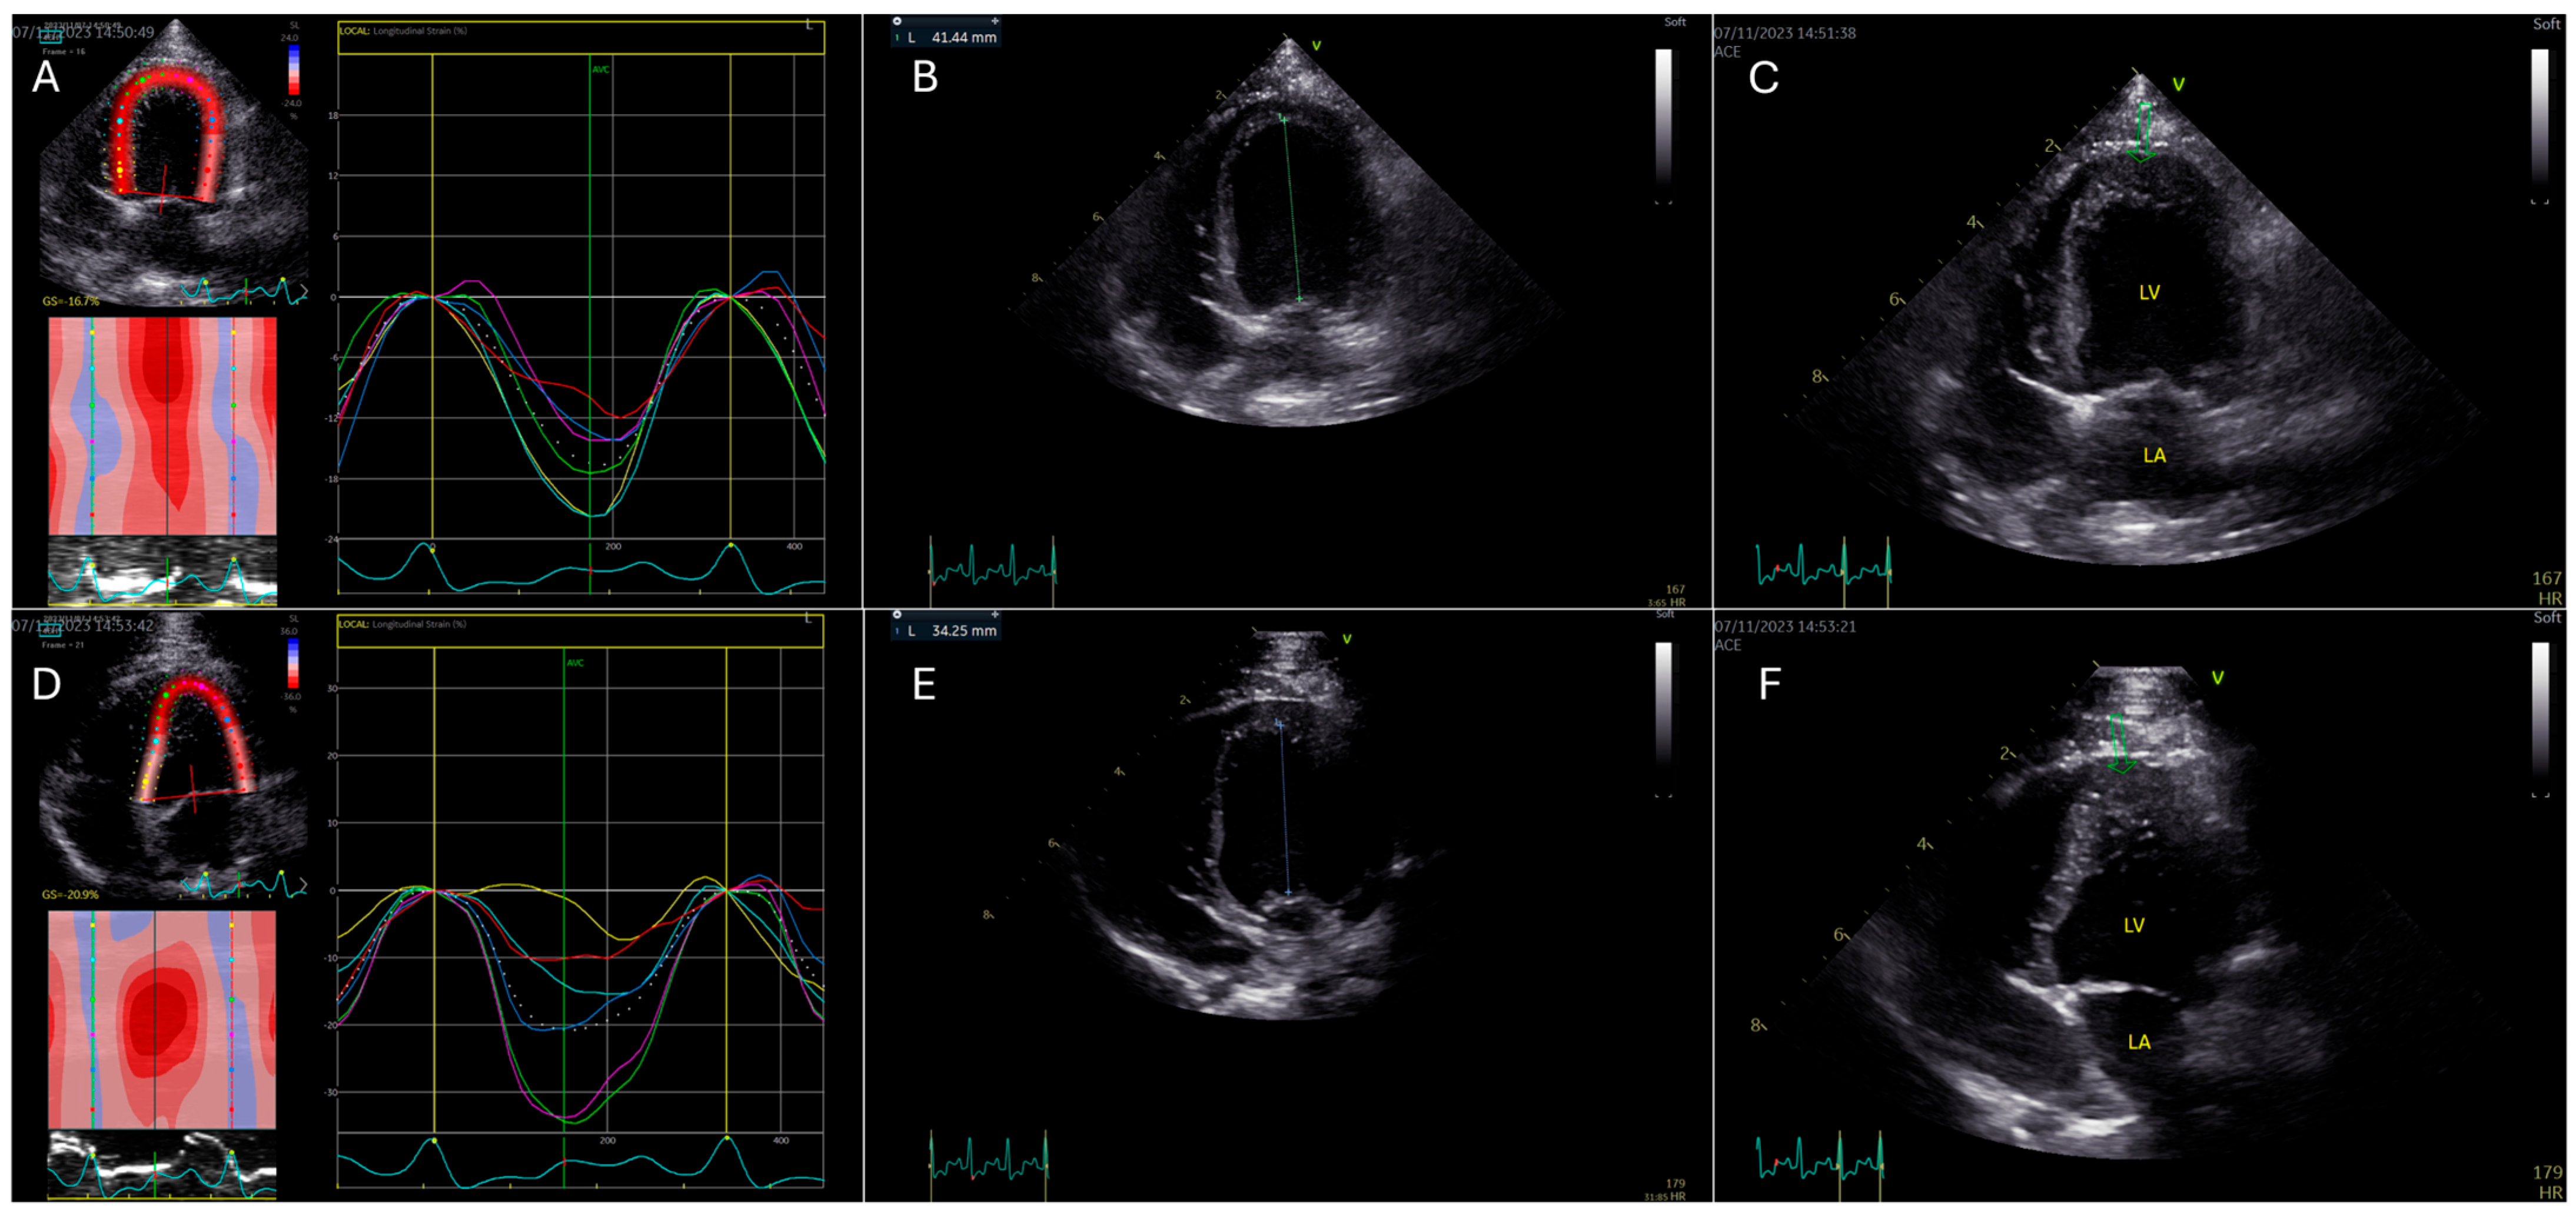

Figure 2. Assessment of global longitudinal strain (GLS) in an optimized versus a foreshortened apical four-chamber (A4C) view in a healthy miniature Bull Terrier using 2D speckle-tracking echocardiography (2D STE). (A): 2D STE trace from an optimized A4C view with appropriate apical imaging. The segmental longitudinal strain curves (colored lines) correspond to the six myocardial segments of the left ventricle in this view, illustrating synchronized myocardial shortening with a calculated GLS of −16.7%. (B): The optimized A4C view in end-diastole demonstrates a long-axis measurement from the mitral annulus to the apex of 41.44 mm. (C): Optimized A4C view in systole. The green arrow indicates the true apex, which appears smooth, pointed, and normally contracting, confirming the absence of foreshortening. (D): Foreshortened A4C view with altered image geometry. The 2D STE-derived strain curves (colored lines) show increased segmental strain values and a falsely elevated GLS of −20.9%, despite identical patient and imaging conditions. (E): Foreshortened A4C view in end-diastole, showing a reduced LV long-axis length of 34.25 mm, consistent with incomplete apical visualization. (F): Foreshortened A4C view in systole, where the apex (green arrow) appears thickened, blunted, and irregular, further confirming suboptimal acquisition.

Furthermore, to evaluate the impact of altered imaging planes, foreshortened A4C views were acquired by positioning the transducer one-to-two intercostal spaces cranial to the standard A4C imaging window (GLSA4C-Foreshortening) (Figure 2). HR manipulation was performed to assess its effect on GLS measurements; this was achieved by inducing mild excitement through auditory cues or treats, resulting in increased HR ranging from 167 to 222 beats per minute (GLSA4C↑HR). To examine the influence of transducer frequency, additional A4C views were obtained using lower frequency transducers, including the M5SC-D and 4Vc transducers (GE Medical, Brondby, Denmark), with frequencies ranging from 1.7/3.3 MHz to 2.3/4.6 MHz (GLSA4C-Frequency).

GLS values from the A4C view were analyzed under different imaging conditions in cohort 1. Significant deviations from the baseline were observed for GLSA4C-Foreshortening and GLSA4C↑HR, with increases in absolute GLS values of 11% and 15.4%, respectively (p < 0.01, Cohen’s d = 0.52, CI: −17.81 to −24.83), and p = 0.02, Cohen’s d = 0.72, CI: −18.07 to −26.23). No significant changes were noted for GLSA4C-Zoom, GLS A4C↑Frame rate, or GLS A4C-Frequency (Table 2).

In the first cohort, GLSA4C measurements were significantly affected by image foreshortening and increased HR, while changes in FR, image zoom, and transducer frequency did not produce statistically significant changes. The increase in absolute GLSA4C values by 11% (p < 0.01) in foreshortened images aligns with findings from human echocardiographic studies using GE EchoPac [15], reinforcing the importance of obtaining a true apical view to prevent GLS overestimation. Foreshortening distorts myocardial deformation vectors and alters strain values, underscoring the need for standardized image-acquisition protocols in veterinary echocardiography. This is particularly relevant since foreshortening is a frequent challenge in small animal echocardiography, where optimal transducer positioning is often constrained by patient size and cardiac conformation [17].